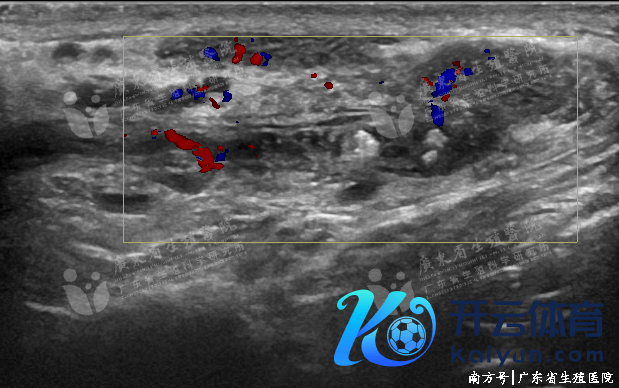

获取性附睾梗阻

也称为继发性附睾梗阻,最常见的原因为附睾急、慢性炎症。附睾管或/和睾丸输出小管呈敷裕性、均匀性细网状彭胀。彭胀附睾管内可见眇小缺点状或黑点状强回声逐步流动。部分患者附睾管及睾丸输出小管呈管状彭胀,内可见密集高回声采集、逐步流动。

炎性附睾梗阻